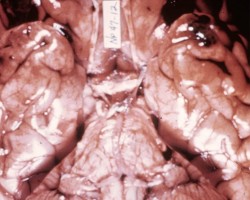

- Cerebral contusions, typically in areas where brain parenchyma rubs against skull bone (i.e. inferior temporal and frontal lobes)

- Coup contusions occur on the side of the trauma.

- Countercoup contusions occur on the opposite side of the site of impact.